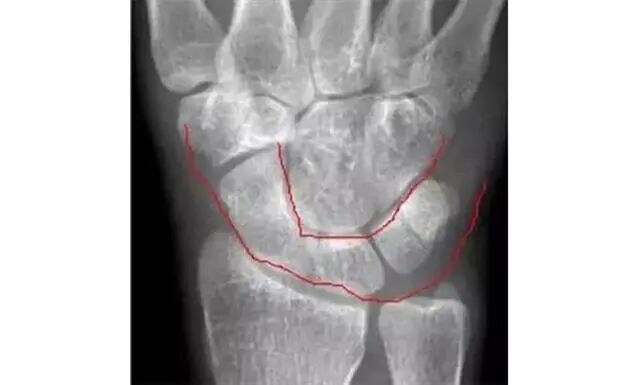

两条弧线 如果不连通 多半有脱位

若显示腕骨弧线不连续或各弧线不平行,或腕掌线M形结构消失,应高度怀疑腕关节不稳或脱位。

侧位显示月骨向掌侧倾斜

1.月骨-三角骨间隙平行关系缺失致掌骨弧线I and II中断。

2.月骨和舟骨平行,而与其他腕骨不平行。

3.舟骨缩短提示向掌侧倾斜。

4.月骨平行于舟骨,其三角形状提示为掌侧倾斜所致。

5.近排腕骨不是一个整体,因为弧线I中断。

诊断:掌屈不稳伴月骨-三角骨关节脱位